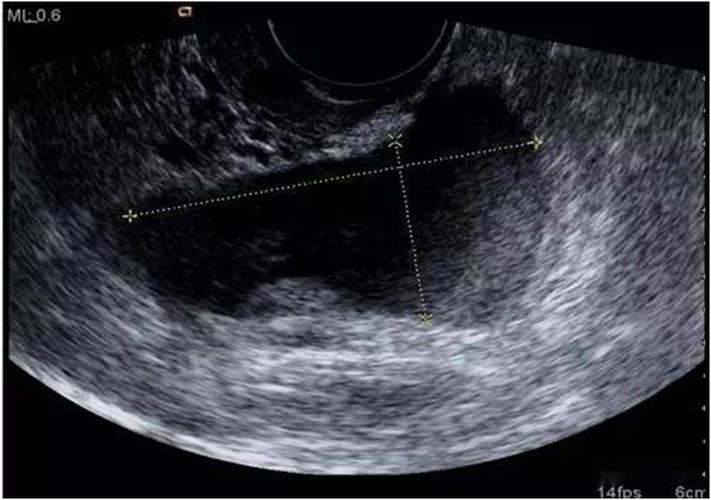

超声典型病例子宫穿孔

超声典型病例:子宫穿孔

子宫穿孔超声表现图

子宫穿孔超声图片

子宫穿孔彩超下表现